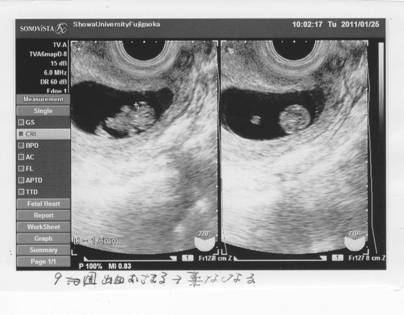

クリニックからの紹介状を携え、昭和藤が丘病院に。

出血層が、近い。

エコーは角度によって見え方が異なる?

エコーの検査で、胎児の大きさが少し小さいように思えたが、

成長は正常である。

機械も違うし角度によっても違うのだろう、と納得。

ただ・・・。

首に浮腫(NT)が見える。

これが大きくなってゆくと、ダウン症などの染色体異常や心疾患の可能性が高くなる。

1週間ではどれほど変化があるか・・・次回は11Wとなる2週間後に検査して、

大きくなっていたら羊水検査をしよう。

後頚部浮腫像(NT)は、妊娠10〜13週に現れ、14〜15週になると消失する。

その10〜13週に観察された際の浮腫の厚さが厚いほど、染色体異常や心臓疾患の危険率が上がると言われている。

とはいえ、正常である可能性の方が絶対的に高いんだけど・・・。